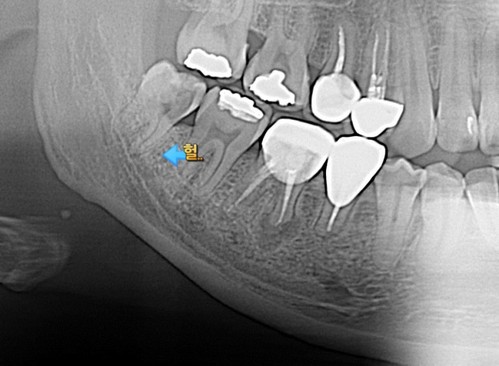

사랑니 뿌리가 신경관과 근접

그 무엇인가 하니 하악 매복사랑니는 열에 아홉은 신경관과 뿌리가 매우 근접하여 발치시 손상될 가능성을 고지하게된다.

나도 환자에게 얘기한다. CT 찍고 위치를 확인하고 되도록 신경에 손상되지 않도록 하겠습니다.